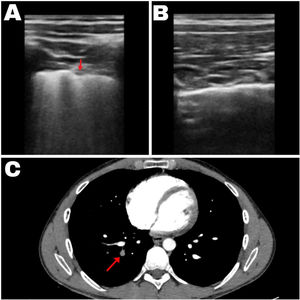

(A) Ecografía pulmonar correspondiente a la zona anatómica posteroinferior derecha del paciente que muestra numerosas líneas B y una consolidación subpleural en forma de cuña bien delimitada, señalado por la flecha. (B) Ecografía pulmonar con líneas A normales en el resto del parénquima pulmonar. (C) Angiotomografía computarizada pulmonar donde se observa un trombo en el vaso señalado por la flecha.

Se realizó una ecografía abdominal a pie de cama que mostró un hígado de morfología normal, vesícula biliar distendida sin litiasis ni engrosamiento de la pared, y vías biliares sin dilatación. Los riñones presentaban un aspecto normal, sin signos de litiasis o dilatación de los sistemas excretores, y la vejiga era normal. La ecografía pulmonar evidenció deslizamiento pleural en todo el parénquima explorado, en la zona posterior inferior derecha se objetivó un aumento abundante de líneas B y alguna condensación subpleural en forma de cuña bien delimitada. El resto de la exploración pulmonar mostraba líneas A sin líneas B evidentes compatibles con la normalidad (fig. 1).

En urgencias, los análisis de laboratorio mostraron glucosa de 93mg/dL, creatinina de 0,7mg/dL y electrolitos en rangos normales. Los marcadores cardíacos presentaron NT-proBNP de 35 pg/mL y troponina I <10 ng/L. El hemograma reveló hemoglobina de 14,4g/dL, leucocitosis de 14.070/μL con neutrofilia del 77% y plaquetas de 293.000/μL. Los parámetros de coagulación estaban dentro de rangos normales, salvo valores de dímero D de 1,07μg/mL. Se realizó una angiotomografía computarizada pulmonar que confirmó TEPA central derecho, afectando la arteria interlobar y las arterias lobares media e inferior, con un área de infarto pulmonar de 6cm en el segmento posterobasal del lóbulo inferior derecho. No se observaron signos de hipertensión pulmonar ni sobrecarga de cavidades derechas (fig. 1).